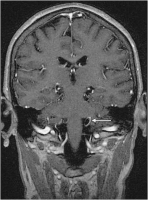

Nervus trigeminus - Arteria cerebelli superior

Abbildung 2: Der Pfeil markiert den Nervus trigeminus rechts im Bereich der Eintrittszone im Hirnstamm. Kranial und lateral wird der Nerv von einer Gefäßschlinge der Arteria cerebelli superior komprimiert.

Keywords: Arteria cerebelli superiorMRTNervus trigeminusNeurochirurgie